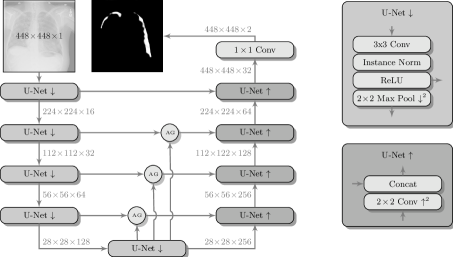

are more advanced network architectures, that have been developed for semantic segmentation, i.e. pixel-level classification. The most commonly employed network in this context is the U-Net [9], which consists of a contracting path resembling a CNN, for the integration of context information, and a corresponding expanding path. This allows to obtain probability maps of the same size as the input image, facilitating the image localization. For this experiment, we employ a U-Net with four layers per path and Attention Gates [8]. Attention gates have been proposed as an alternative to a detection component and they are employed in order to facilitate the segmentation of an object of interests. Furthermore, the proposed architecture uses instance normalization instead of commonly used batch normalization in order to harmonize the input data (cf. Fig. 3).

To increase the variability of the available data, we augmented the dataset by translating, scaling, rotating, horizontal flipping, windowing, and adding Poisson noise. Input images for CNN and FCN have been created by cropping a centered patch of from the original images resized to . For MIL we cropped overlapping patches out of the image resized to (cf. Fig. 2). In training, we used the Adam optimizer with default parameters and , a batch size of 16, and exponentially decreasing learning rate (LR). Refer to Table 1 for an overview of the parameters and to Fig. 4 for the receiver operating characteristic (ROC) analysis we performed to assess the model performance.